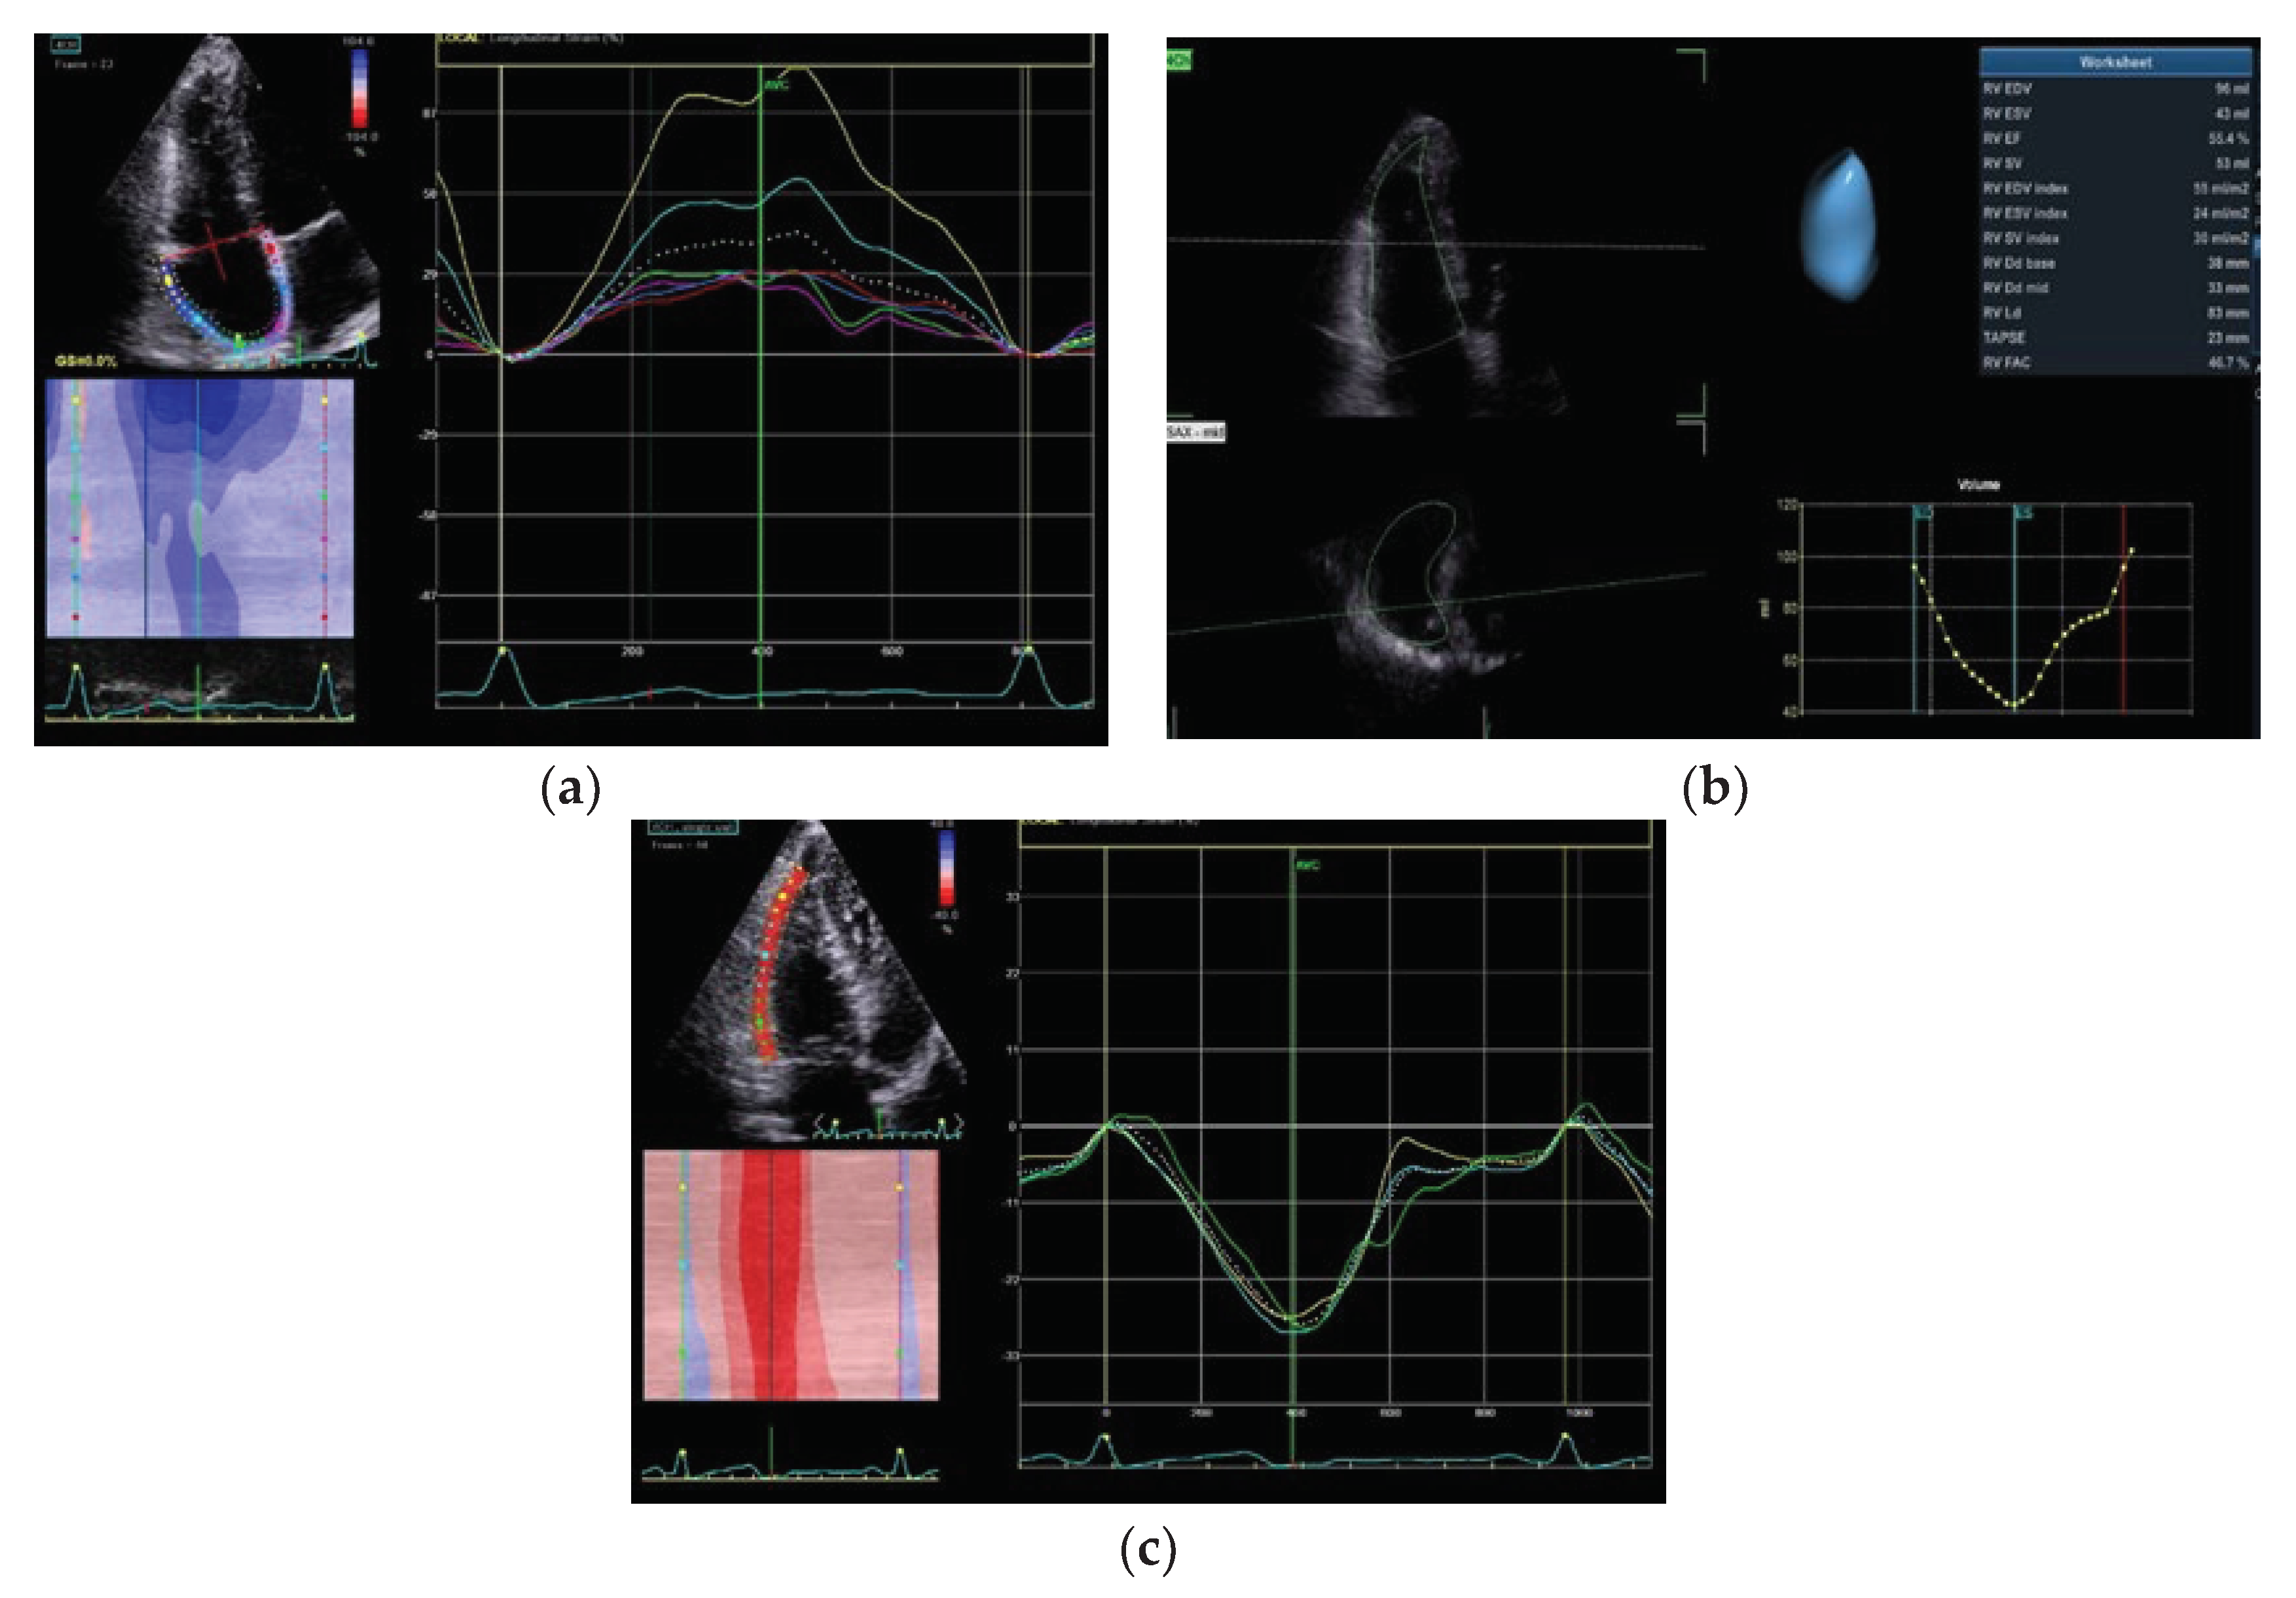

5.1. RV Function Assessment with 3D Echocardiography

5.2. Right Ventricle Speckle Tracking

5.3. Right Atrium Volume and Strain

- Inaba, T.; Yao, A.; Nakao, T.; Hatano, M.; Maki, H.; Imamura, T.; Shiga, T.; Yamazaki, T.; Sonoda, M.; Kinugawa, K.; Shiota, T.; Suzuki, J.; Takenaka, K.; Hirata, Y.; Nagai, R. Volumetric and Functional Assessment of Ventricles in Pulmonary Hypertension on 3-Dimensional Echocardiography. Circ J 2013, 77, 198–206. [Google Scholar] [CrossRef]

- Jone, P. N.; Schäfer, M.; Pan, Z.; Bremen, C.; Ivy, D. D. 3D echocardiographic evaluation of right ventricular function and strain: a prognostic study in paediatric pulmonary hypertension. Eur Heart J Cardiovasc Imaging 2018, 19(9), 1026–1033. [Google Scholar] [CrossRef]

- Lattanzio, M.; Scelsi, L.; Golino, M.; Lattuada, M.; Raineri, C.; Turco, A.; Giuntini, C.; Ceriani, F.; Curti, M.; Bonelli, A.; Piacentino, F.; Venturini, M.; Ghiringhelli, S.; Morandi, F.; De Ponti, R.; Ghio, S. Assessment of right ventricle in pulmonary arterial hypertension with three-dimensional echocardiography and cardiovascular magnetic resonance. J Cardiovasc Med (Hagerstown) 2021, 22(12), 929–936. [Google Scholar] [CrossRef]

- Ikeda, S.; Tsuneto, A.; Kojima, S.; Koga, S.; Nakata, T.; Yoshida, T.; Eto, M.; Minami, T.; Yanagihara, K.; Maemura, K. Longitudinal Strain of Right Ventricular Free Wall by 2-Dimensional Speckle-Tracking Echocardiography Is Useful for Detecting Pulmonary Hypertension. Life Sci 2014, 111, 12–17. [Google Scholar] [CrossRef]

- Shiino, K.; Sugimoto, K.; Yamada, A.; Takada, K.; Kawai, H.; Sugimoto, K.; Takahashi, H.; Takagi, Y.; Iwase, M.; Ozaki, Y. Usefulness of Right Ventricular Basal Free Wall Strain by Two-Dimensional Speckle Tracking Echocardiography in Patients with Chronic Thromboembolic Pulmonary Hypertension. Int Heart J 2015, 56, 100–104. [Google Scholar] [CrossRef]

- Haeck, M. L.; Scherptong, R. W.; Marsan, N. A.; Holman, E. R.; Schalij, M. J.; Bax, J. J.; Vliegen, H. W.; Delgado, V. Prognostic value of right ventricular longitudinal peak systolic strain in patients with pulmonary hypertension. Circ Cardiovasc Imaging 2012, 5(5), 628–636. [Google Scholar] [CrossRef] [PubMed]

- Motoji, Y.; Tanaka, H.; Fukuda, Y.; Ryo, K.; Emoto, N.; Kawai, H.; Hirata, K. Efficacy of right ventricular free-wall longitudinal speckle-tracking strain for predicting long-term outcome in patients with pulmonary hypertension. Circ J 2013, 77(3), 756–763. [Google Scholar] [CrossRef] [PubMed]

- Hulshof, H. G.; Eijsvogels, T. M. H.; Kleinnibbelink, G.; van Dijk, A. P.; George, K. P.; Oxborough, D. L.; Thijssen, D. H. J.; Opondo, M. A. Prognostic value of right ventricular longitudinal strain in patients with pulmonary hypertension: a systematic review and meta-analysis. Eur Heart J Cardiovasc Imaging 2019, 20(4), 475–484. [Google Scholar] [CrossRef] [PubMed]

- Moceri, P.; Bouvier, P.; Baudouy, D.; Dimopoulos, K.; Cerboni, P.; Wort, S. J.; Gatzoulis, M. A. Cardiac remodelling amongst adults with various aetiologies of pulmonary arterial hypertension including Eisenmenger syndrome-implications on survival and the role of right ventricular transverse strain. Eur Heart J Cardiovasc Imaging 2017, 18(11), 1262–1270. [Google Scholar] [CrossRef]

- Deng Y, Guo SL, Wu WF, Wang Q, Su HY, Tan Z, Wang F, He QY. Right Atrial Evaluation in Patients With Pulmonary Hypertension: A Real-time 3-Dimensional Transthoracic Echocardiographic Study. J. Ultrasound Med. 2016, 35(1), 49-61. [CrossRef]

| RV speckle tracking | 4Ch view. RV free wall may be not well-visualized | Moderate to high | • Limited studies on specific populations • Image quality |

| RA strain | 4Ch view may be not well-visualized | No data | • Limited studies on specific populations • Image quality |